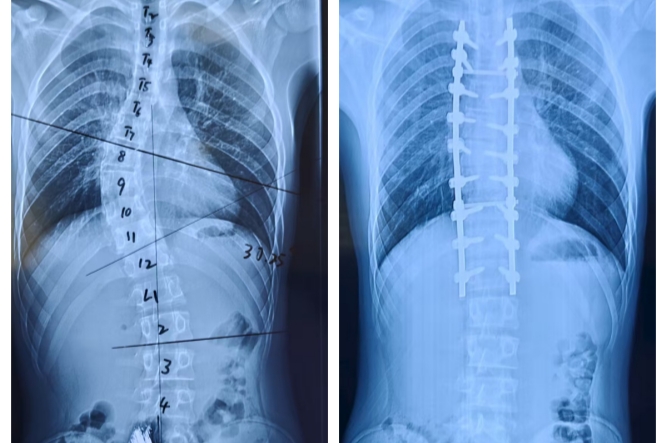

7年前,小卓的家人發(fā)現(xiàn)其脊柱側彎,但因當地醫(yī)療條件有限未能系統(tǒng)治療。隨著生長發(fā)育,他的脊柱畸形逐漸加重,出現(xiàn)明顯的“剃刀背”、雙肩失衡等癥狀,不僅影響身體功能,更給他帶來了沉重的心理負擔。

近日,來自青海玉樹患有嚴重脊柱側彎合并脊髓空洞癥的15歲藏族少年小卓(化名),在晉城大醫(yī)院多學科團隊的協(xié)作下,成功接受了高難度的脊柱截骨矯正手術,挺直腰桿,重獲新生。、

入院后,脊柱骨科團隊立即為小卓進行了全面的術前檢查。各項檢查結果均顯示:先天性脊柱側彎、脊髓空洞、骶1隱性裂。

骨科、心血管內科、呼吸與危重癥醫(yī)學科、麻醉科、臨床營養(yǎng)科等多學科會診,制定周密的治療方案:一是小卓需進行頸頜吊帶+骨盆牽引,糾正一定的畸形角度;二是針對小卓BMI偏低的情況定制科學食譜,為手術筑牢營養(yǎng)關;三是實施脊柱截骨矯正手術+內固定術。

經過7個小時的手術,手術成功完成。術后醫(yī)護團隊24小時密切監(jiān)護小卓的恢復情況,術后康復治療對于脊柱功能的全面恢復至關重要,康復師第一時間為小卓進行功能康復鍛煉。

經過16天的精心治療,小卓的脊柱外觀明顯改善,實現(xiàn)了真正的脫胎換骨,康復出院。